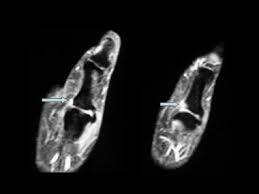

MRI For Left Thumb

Medifyhome has collaborated with the best pathology laboratories that are NABL and NABH certified and follow ISO safety guidelines to provide the best MRI For Left Thumb at an affordable price for needy individuals. An MRI for the left thumb is a non-invasive diagnostic tool that uses strong magnetic fields and radio waves to create detailed images of the internal structures of your thumb. Whether you’re dealing with an injury, unexplained pain, or a medical condition affecting the thumb, an MRI provides doctors with a clear, high-resolution view of the bones, muscles, tendons, ligaments, and nerves in this small but essential part of your hand. The thumb plays a critical role in our daily activities, from gripping to fine motor tasks, and any problem affecting it can significantly impact quality of life. MRI is particularly useful for diagnosing conditions that affect both soft tissues and bones, such as ligament tears, tendon injuries, fractures, arthritis, or nerve issues that might not be visible through other imaging techniques like X-rays. With its ability to provide a comprehensive look at the thumb’s anatomy without the need for surgery or invasive procedures, MRI is a valuable tool for identifying the underlying causes of thumb pain and discomfort. By understanding how MRI for the left thumb works and when it’s recommended, patients can feel more confident in their healthcare decisions and ensure they receive the most accurate diagnosis and effective treatment for their condition.